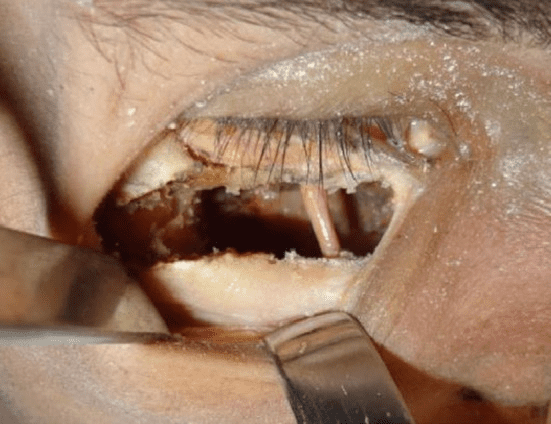

It moves cheekbones upward, give so much under eye support and even change orbital shape. Also widen face and change gonial angle. Is it modified lefort 3?